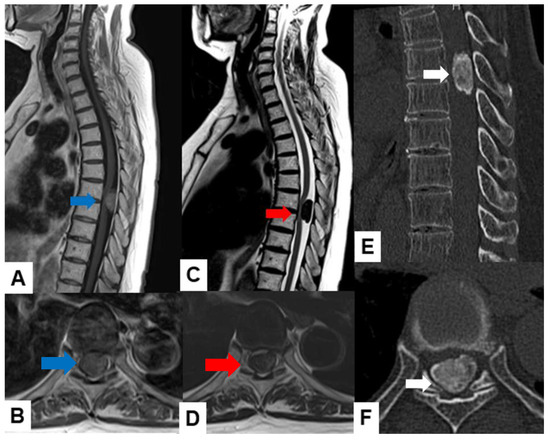

Meningiomas usually indicate isointensity in both T1- and T2-weighted MR imaging and are enhanced homogeneously (Figure 3) [35]. Meningiomas are sometimes calcified and are recognized in CT (Figure 4). The key points of a differential diagnosis of meningioma and schwannoma are in Table 4.

Figure 4.

Sixty-eight F, spinal meningioma. (A) Enhanced T1-weighted midsagittal image, (B) enhanced T1-weighted axial image at T7/8, (C) T2-weighted midsagittal image, (D) T2-weighted axial image at T7/8, (E) midsagittal reconstruction CT, and (F) axial CT at T7/8. Red arrows indicate tumor, and blue arrows show tumor enhancement. The tumor is calcified (white arrows).